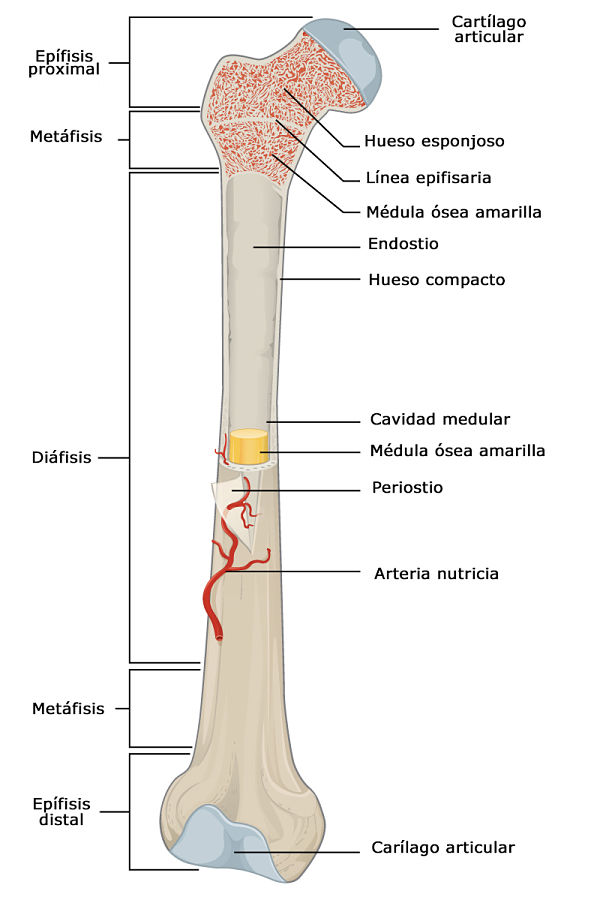

La metáfisis es la zona de los huesos largos que se encuentra entre la epífisis (parte superior e inferior) y la diáfisis (parte central). En los huesos de niños y adolescentes que se encuentran en período de crecimiento, la metáfisis está separada de la epífisis por una zona transicional denominada cartílago de crecimiento, la cual permite que los huesos se alarguen.

Una vez que termina el desarrollo óseo, alrededor de los 18 años para las mujeres y de los 21 años en los hombres, el cartílago de crecimiento se calcifica y la metáfisis se une definitivamente con la epífisis. Esta unión se conoce como línea epifisaria.

Histológicamente esta parte del hueso está conformada por tejido óseo trabecular o esponjoso, es decir, que contiene médula ósea, que es la encargada del desarrollo de células sanguíneas y su liberación al torrente.

El área de la metáfisis está ricamente vascularizada y estos vasos sanguíneos se encargan de irrigar el cartílago de crecimiento que se encuentra cerca de ella.

Los huesos largos constan de tres partes, las epífisis que se ubican en los extremos, la diáfisis, que forma la parte media del hueso, y la metáfisis que se ubica entre estas dos porciones.

La metáfisis es un área que se encuentra en los huesos largos. Durante el crecimiento está separada de la epífisis por un cartílago celular especializado, el cual se llama cartílago de crecimiento.

En grandes huesos como el fémur, la tibia o el radio, se encuentran dos metáfisis. Una en la parte superior, o proximal, y una inferior o distal. Huesos largos más pequeños, como los interfalángicos o metacarpianos, tienen una sola metáfisis.

El tejido óseo que forma la metáfisis es de tipo trabecular o esponjoso. Este tipo de tejido soporta bien el impacto de rebote y transfiere las vibraciones de estos golpes al tejido óseo duro o compacto. Además tiene una arquitectura que consta de pequeños tabiques óseos dentro de los cuales se encuentra la médula ósea.

Dentro de la médula ósea se forman las células sanguíneas que serán liberadas hacia la circulación.

La metáfisis es una parte fundamental del hueso que contiene una red complicada de vasos sanguíneos que se encargan de nutrir los cartílagos cercanos.